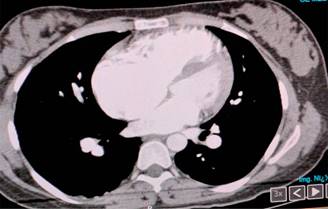

A su llegada, se continuó manejo con oxígeno complementario. Se integran diagnósticos presuntivos de insuficiencia respiratoria aguda, probable tromboembolia pulmonar; se inicia manejo para sospecha diagnóstica a base de anticoagulación plena y tratamiento con opioide, con lo que remite el dolor. Se solita ECG en donde se reporta frecuencia cardiaca de 110 latidos por minuto, con inversión de la onda T de V1-V6 (Figura 1). Gasometría arterial: pH 7.47, pCO2 17, pO2 45, SatO2 84%, HCO3 17.5; durante su estancia presenta desaturación progresiva, hasta llegar a 68%, por lo que incrementan parámetros de oxigenación. Se solicita angiotomografía, la cual reporta: datos sugestivos de hipertensión pulmonar (Figura 2), por lo que se inicia manejo con inhibidores de la fosfodiesterasa.